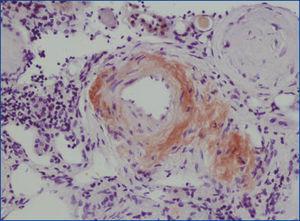

Se decide realizar una biopsia renal, que muestra 26 glomérulos, de los cuales 17 están esclerosados. En algunos de los glomérulos no esclerosados se observan muy focales depósitos nodulares de material hialino eosinófilo, acelular y débilmente ácido peryodico (PAS+) más frecuente en el polo vascular (figura 1), material que se observa también y en mayor cantidad en intersticio y en pared de arterias y arteriolas (figura 2). Este material se tiñe con la técnica de rojo congo (figura 3 y figura 4), tinción que desaparece tras el tratamiento con permanganato, y muestra birrefringencia verde manzana con luz polarizada. Con técnicas de inmunohistoquímica, el material acelular muestra tinción con amiloide A (figura 5). Se observa además una fibrosis intersticial y atrofia tubular moderadas (20 %). Con estos datos histológicos, se realiza el diagnóstico de amiloidosis renal secundaria (AA) con afectación glomerular, vascular e intersticial.

Figura 2. Depósitos de amiloide en arterias con hematoxilina-eosina.